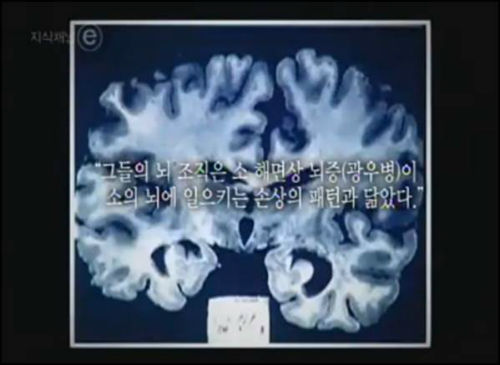

한편, 김진혁 PD는 2008년 EBS ‘지식채널ⓔ’에서 광우병을 다룬 ‘17년 후’ 편을 제작한 후 정기 인사를 통해 교체돼 보복성 인사가 아니냐는 논란을 일으킨 바 있다. 당시 EBS 경영진은 광우병을 다뤘다는 이유로 2008년 5월 12~16일 밤 각 1회씩 총 6회의 전파를 탈 예정이었던 ‘17년 후’편의 잔여 방영 계획을 취소하라 지시했다.